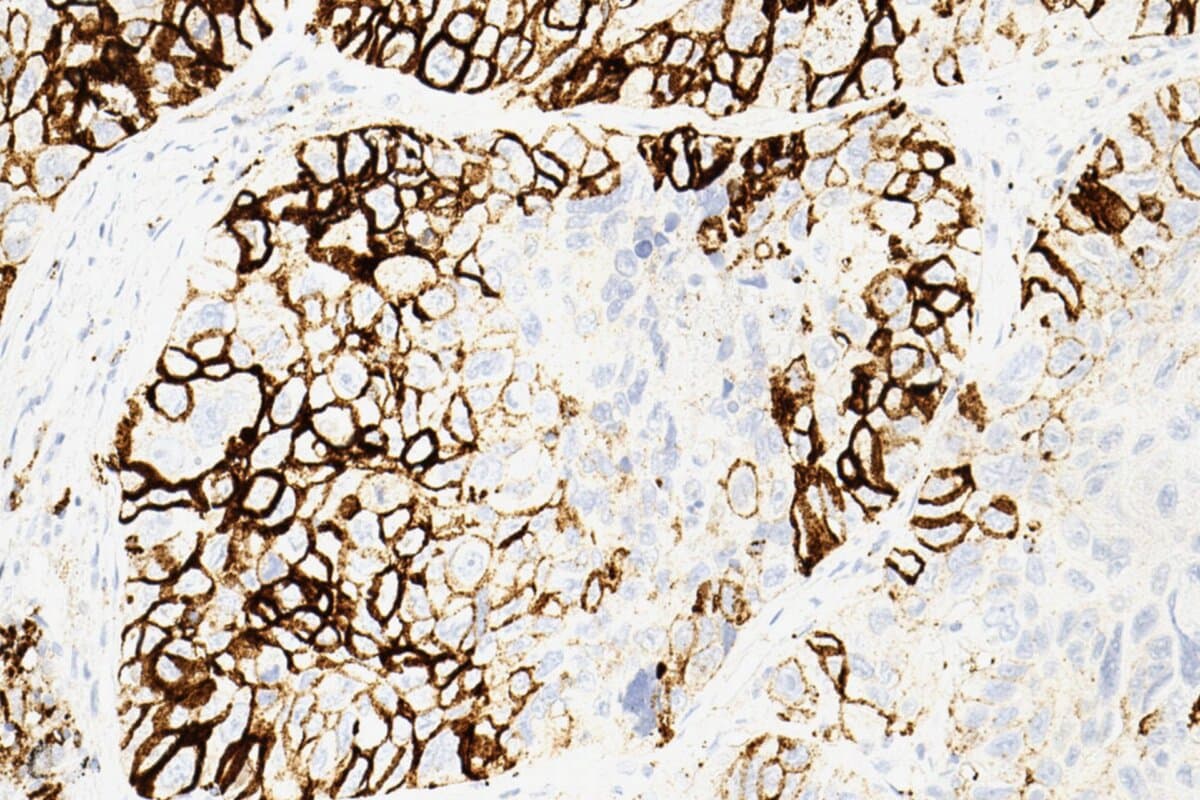

- digitalisierten Gewebeproben aus pathologischen Untersuchungen und

Mithilfe von maschinellen Lernverfahren kombinierte das Team die verfügbaren Informationen zu mehreren unterschiedlichen Scoring-Systemen, die sie etablierten Biomarkern wie PD-L1, der Tumor Mutational Burden (TMB) oder Tumor-infiltrierende Lymphozyten (TILs) gegenüberstellten.